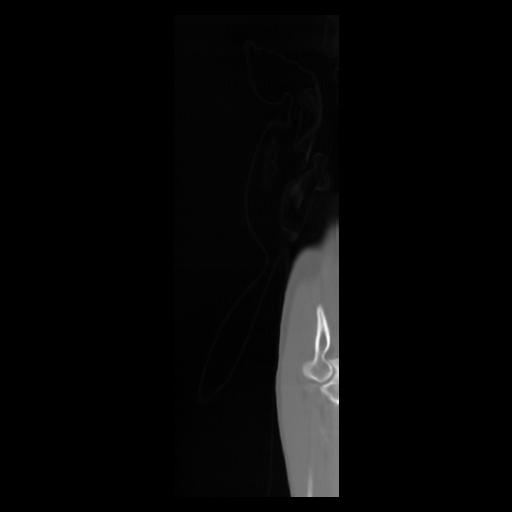

30 CUERPO,CE,Sagittal,3.000,CUERPO,Sagittal,